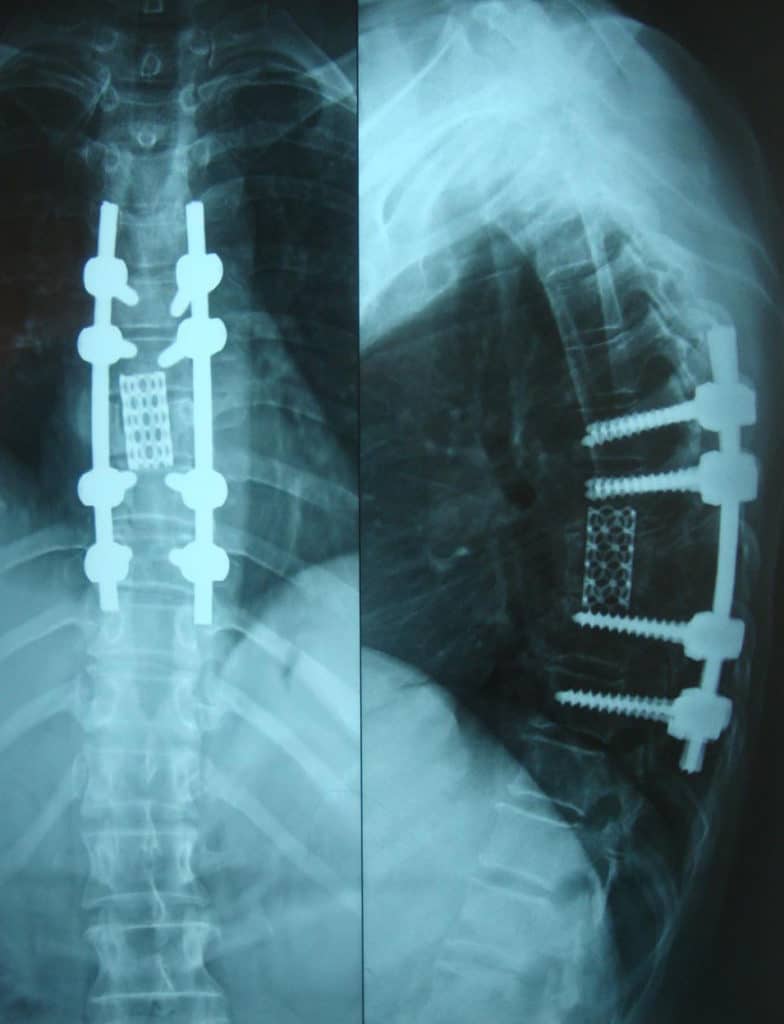

From www.chibumd.com

Adult Degenerative Scoliosis Chibuikem Akamnonu, MD Scoliosis Caused By Degenerative Disc Disease Degenerative disk disease occurs when your spinal disks break down. Degenerative scoliosis may be caused by degeneration of the discs (which separate the vertebrae) or arthritis in the joints that link. Degenerative scoliosis is an abnormal spinal curve caused by the deterioration of spinal disks and connective. Most cases of scoliosis are mild, don’t cause symptoms. Typical signs and symptoms. Scoliosis Caused By Degenerative Disc Disease.